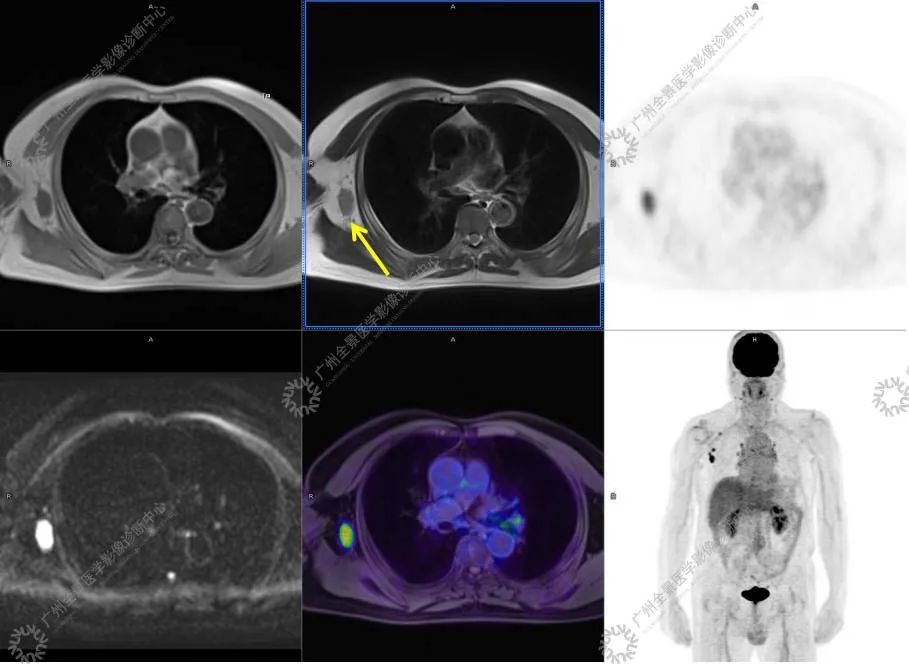

结合影像及实验室检查,临床最终考虑 IgG4 相关性疾病。

●18FDG-PET/CT 作为一种解剖和功能结合新的显像方法,IgG4-RD 的诊断及鉴别诊断中存在着巨大的优势:

●18FDG 对于炎性病变的检出有很高的敏感性, 但特异性较差,结合 CT 解剖影像可以明显的提高诊断的准确率。

●对于因各种原因无法进行增强检查的患者,特别是肾功能受损的患者, 18FDG-PET/CT 可以作为一种很好的替代方法,几乎不对肾功能产生任何影响。

●18FDG-PET/CT 扫描作为一种全身检查,有着传统影像学局部扫描无法比拟的优势,PET/CT 扫描不仅可以发现以临床症状为导向的局部病灶,更可以发现远隔部位的受累病灶。